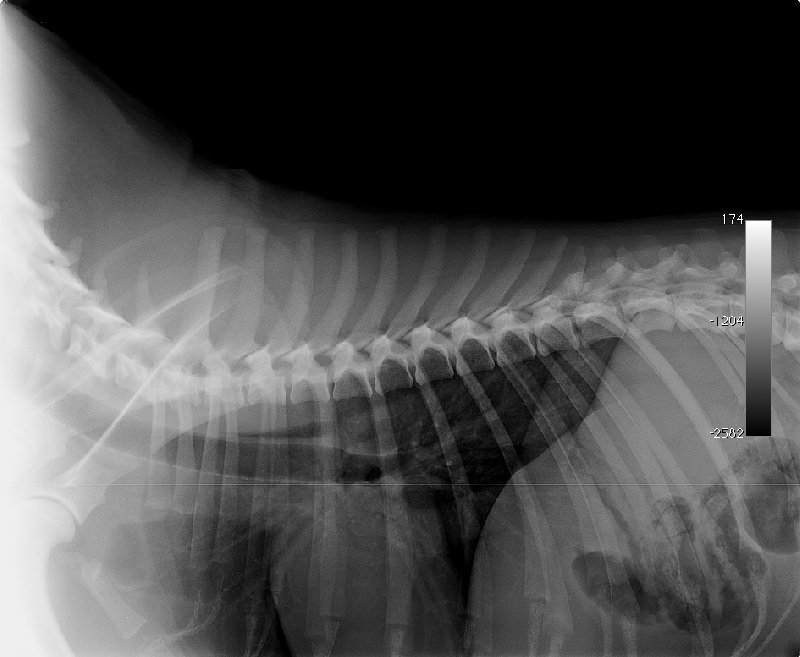

SPONDYLOSE